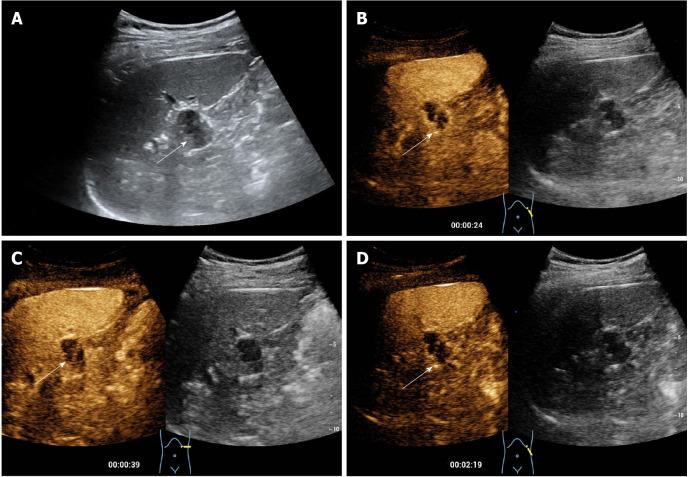

Herein, we present a case involving a 32-year-old male who had a complex cystic lesion in the tail of the pancreas revealed by conventional ultrasound. The lesion was misdiagnosed as a pancreatic cystadenoma because of its confusing anatomic location, as well as due to its peripheral nodular and internal septal enhancement patterns on contrast-enhanced ultrasound. After multidisciplinary discussion, the patient finally underwent laparoscopic pancreatic body and tail resections. Postoperative pathology demonstrated the lesion to be a cavernous hemangioma arising from the IPAS.

Cavernous hemangioma in the intrapancreatic accessory spleen may mimic pancreatic cystadenoma, which is a condition with the potential to be malignant. Imaging follow-ups or surgical interventions may be helpful for the exclusion of malignant risks in complicated cystic lesions, especially those with parietal and septal enhancements.